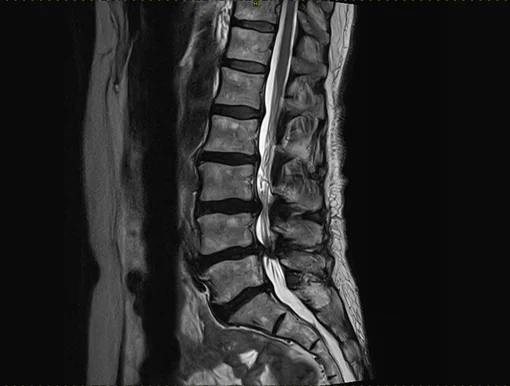

According to biological aging, degeneration runs in different phases. Initially, the water retention capacity decreases, resulting in a possible painful segmental hypermobility. During this phase, diagnostic imaging is often inconclusive. X-rays can show retrolisthesis, a reverse sliding of the upper vertebra over the lower vertebra. In the MRI, the affected intervertebral disc appears plain black (black disc), sometimes a small collection of fluid is seen in the rear fiber ring (annular tear), which is accepted as apparent pain symptom.

During the further course of the process, substance of the intervertebral disc is decreasing, disc height is diminished, leading, regardless of protrusions and/or herniations, to narrowing of the nerve exits, a lateral narrowing of the spinal canal called lateral stenosis. Advanced stages of degeneration lead to a complete loss of disc height causing complete narrowing of the spinal canal (central stenosis). X-rays and MRI show typical signs as well. Although increased stiffening can be assumed in the advanced stages, segmental instabilities can regularly be found, causing pain.